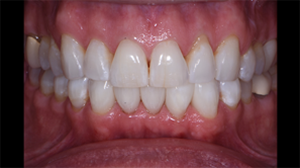

Fig. 5: Injection molding and shaping of tooth #24 completed. Tooth #25 matrixed and ready for injection molding.

Fig. 6: Tooth #25 injection molding completed and matrices yet to be removed. Critical to injection molding is the excess volume, which creates a monolithic inner core while driving defects to the outer layer. This outer layer is subsequently removed, while the inner core is trimmed with a disc to achieve the final desired shape.

Fig. 7: Labial view of the completed case. Four black triangles closed between teeth #22-27.

Fig. 10: Retracted views. Teeth are still dehydrated, but color blending with Filtek Universal can already be appreciated.